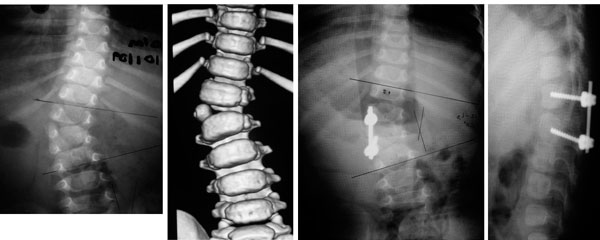

Paciente de 1 año y 8 meses con escoliosis congénita progresiva, se realizo resección de hemivertebra con colocación de tornillos transpediculares.